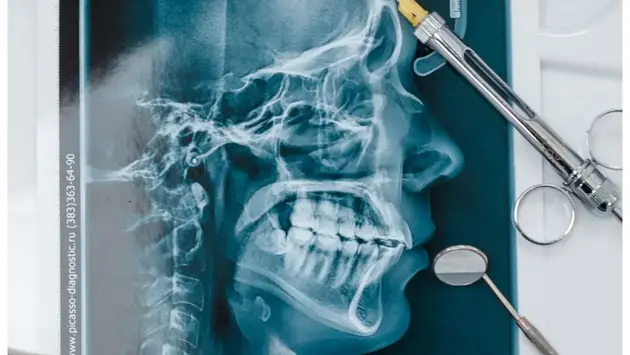

Согласно статистике, порядка 50, а то и 70% людей за свою жизнь сталкивались с проблемами височно-нижечелюстного сустава в различных формах проявления и степенях выраженности. Появление таких симптомов как хруст, щелчок, боль, шум в ушах и нарушении открывания рта в области височно-нижечелюстного сустава — точный повод обратиться к врачу специалисту. Лечением подобных паталогий занимаются врачи гнатологи. О симптомах, диагностировании и лечении рассказывает врач ортодонт-гнатолог Макаревич Элина.

Подобные проблемы в суставе носят прогрессирующий характер, и при отсутствии оказанной помощи и своевременного лечения они могут привести к значительному снижению функции качества жизни: регулярные и сильные боли в области ВНЧС, нарушение открывания рта и движений нижней челюсти, затруднённое и болезненное жевание а также ухудшение осанки и асимметрия лица.